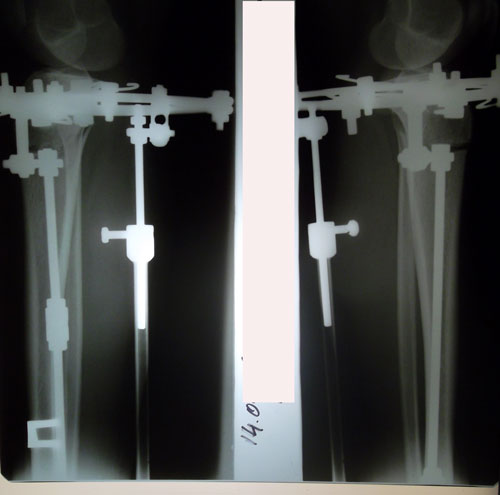

Исходник - 22 года.

Ротация справа под вопросом.

Дата операции 29.03.2016г.